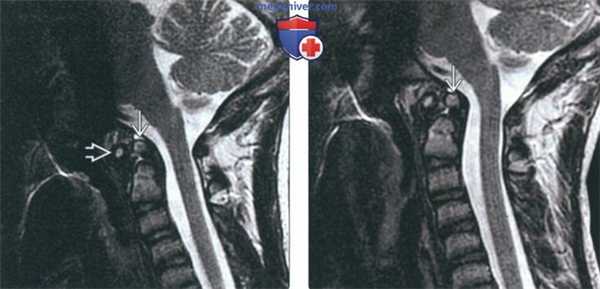

- Исследование можно выполнить в положении сгибания и разгибания, что позволяет оценить стабильность и влияние аномалии на спинной мозг(Слева) На сагиттальном Т2-ВИ, полученном в положении сгибания, видна расположенная несколько кпереди относительно С2 дистопичная зубовидная кость. Сохраняется нормальное расстояние между передней дугой С1 и костью, однако отмечается изменение положения кости относительно С2 (атлантоаксиальная нестабильность) по сравнению с изображениями в нейтральном положении и положении разгибания.

(Справа) Это сагиттальное Т2-ВИ получено в положении разгибания и отражает нормальное расположение зубовидной кости. В положении сгибания эта кость смещается кпереди, что свидетельствует об атлантоаксиальной нестабильности. (Слева) КТ шейного отдела позвоночника, сагиттальный срез: врожденное сращение передней дуги С1 и крупной зубовидной костив. Нормальные взаимоотношения между скатом В и зубовидной костью сохранены. Субаксиальные сегменты шейного отдела позвоночника во всех отношениях нормальны, признаков каких-либо других аномалий сегментации не выявлено.

(Слева) На сагиттальной МРТ (Т2 ВИ) в положении сгибания определяется переднее положение дистопической зубовидной костив относительно С2. Расстояние между передней дугой С1 и зубовидной костью сохранено; определяется нарушение положения зубовидной кош относительно С2 по сравнению с изображениями в нейтральном положении и при разгибании (атланто-аксиальная нестабильность).

(Справа) На сагиттальной MPT (Т2 ВИ) в положении разгибания у этого же пациента положение зубовидной кости обычное. На сагиттальной МРТ (Т2 ВИ) в положении сгибания определялось переднее смещение зубовидной кости, свидетельствующее об атланто-аксиальной нестабильности.2. Рентгенография при зубовидной кости: